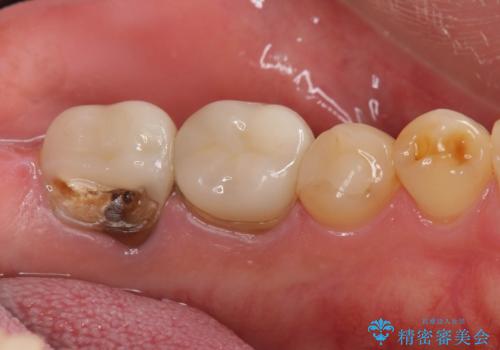

割れたクラウン 再発した虫歯の治療

- 「他院で治療したクラウンが破損したまま放置してしまった、治療したい。」、とセラミック治療を希望され来院されました。

欠けたクラウンの下には虫歯が再発し、このまま放置すると抜歯を余儀なくされる状態です。

虫歯をマイクロスコープを用いて丁寧に除去した後、ジルコニアセラミッククラウンによるクラウン製作を行います。

仕上がりの色調や自然さに満足いただくことができました。